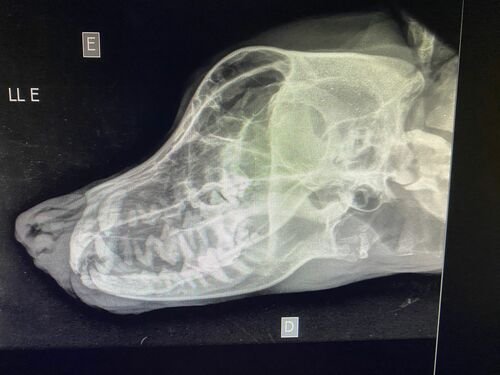

Infelizmente no dia 15/04 ele foi vítima de um atropelamento, como consequência teve fratura no maxilar e na patinha, e também está com processo inflamatório no pulmão!Os tutores não tem condições para arcar com todos os gastos, porque além disso tudo, o dono/companheiro do Campeão é portador do Autismo, e ele precisa URGENTEMENTE do seu melhor amigo em casa novamente!A cirurgia das fraturas está no valor de $3000. Além disso ele precisa de internação e controle com medicação no pós cirurgico.